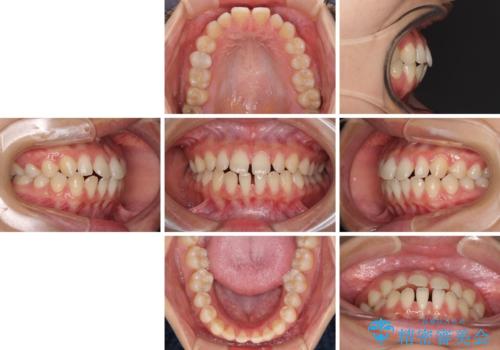

隙間だらけの歯列 インビザラインで改善

- 前歯の上下スペースと前歯の隙間を気にして来院された患者様です。

飲み込みや話をするときに舌を突出させる癖が強くあり、それが原因でスペースが空いていました。

舌癖を改善するためのトレーニングを行いながら、インビザラインにより上下の前歯の隙間を閉じていくこととしました。

空隙歯列(すきっ歯)は、舌の突出癖をある程度改善できたとしても、後戻りにより隙間が開きやすいと言われています。

裏側から細いワイヤーで保定するとともに、睡眠時のマウスピース装着を徹底していただくことで、後戻りを最小限にとどめます。